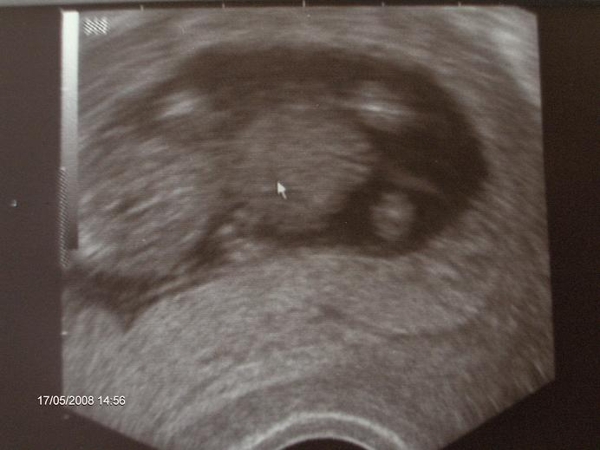

Witam ja tez bym chciala miec z kim popisac,jestem w ciazy po raz 4,tz5,ale mam 3 dzieci 3 dziewczyny,mialam jedno poronienie i teraz jestem ciagle pod strachem,jestem w 14 ygodniu ciazy,od prawie 2 tygodni czuje ruchy malenstwa.pozdrawiamWitam